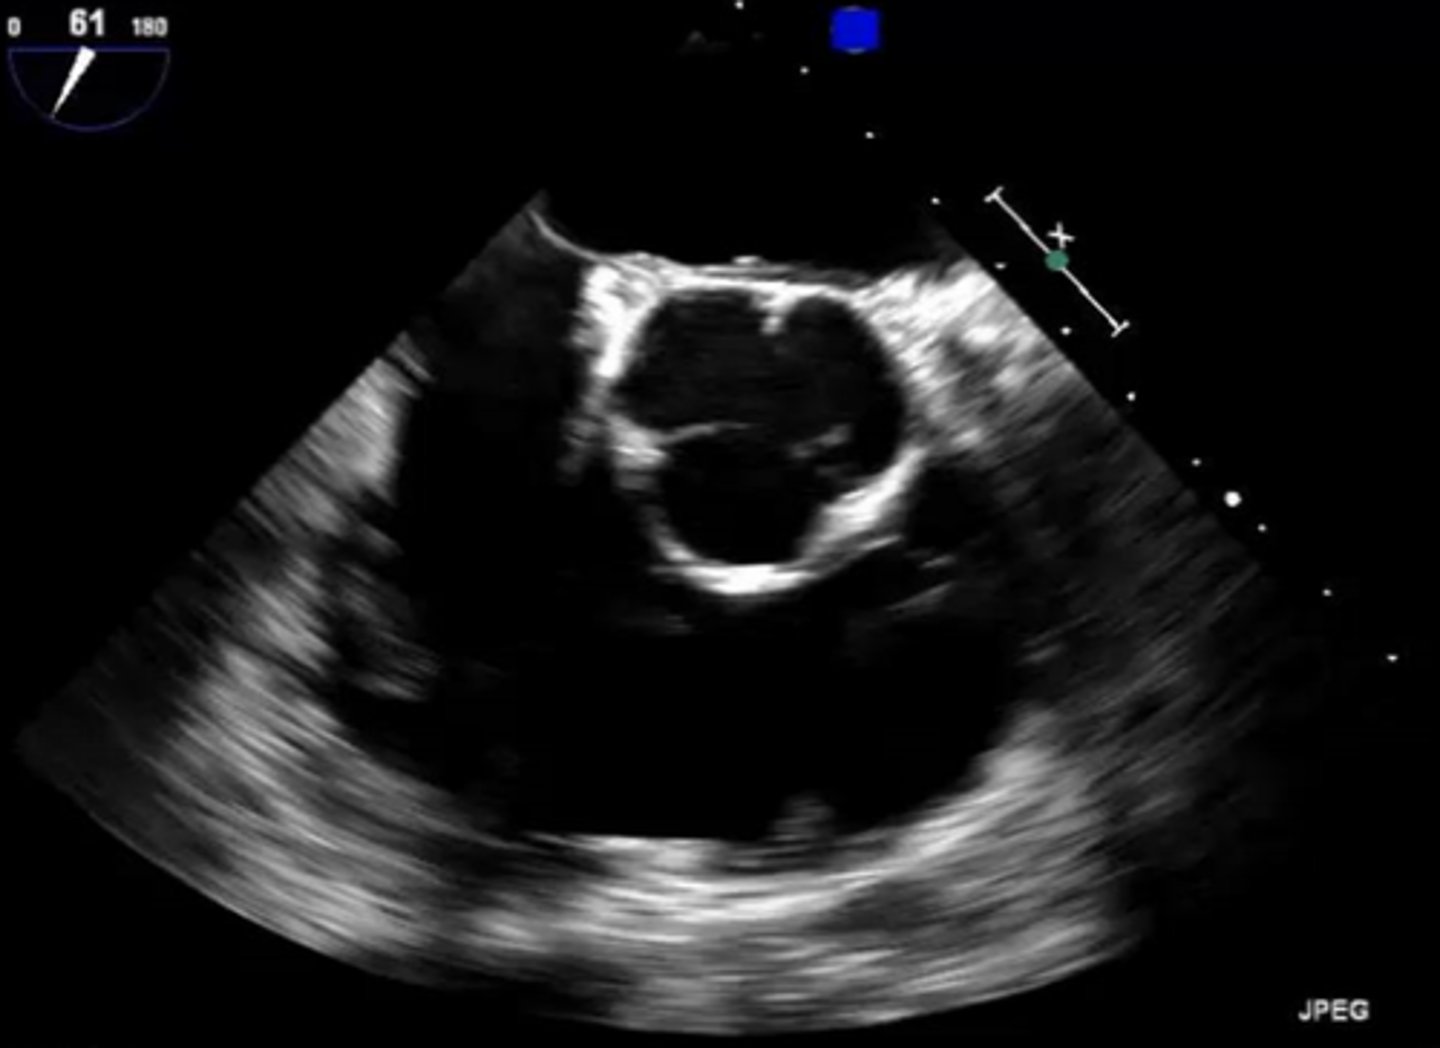

AoV 3CA (left cusp)

non-coronary cusp

AoV 3CA (right cusp)

right coronary cusp

MV 3CA (left leaflet)

posterior mitral valve leaflet

MV 3CA (right leaflet)

anterior mitral valve leaflet